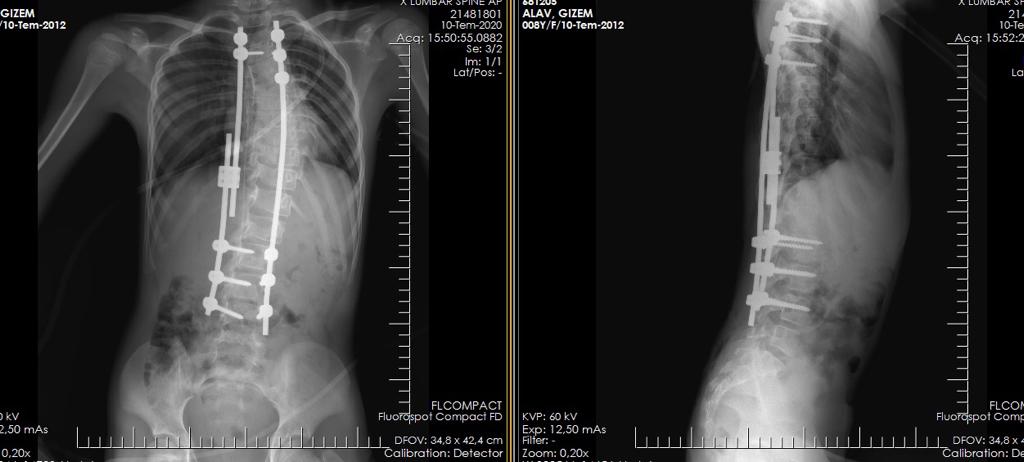

12 yaş Skolyoz hastası ameliyat öncesi filmleri

12 yaş hastaya kalıcı ameliyat ile tedavi tamamlanmış.